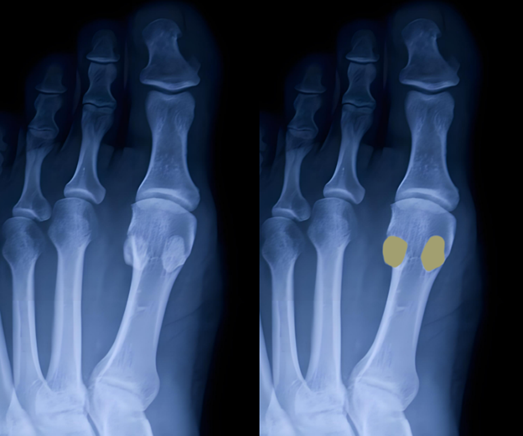

图6:拇趾籽骨

图7:籽骨骨折